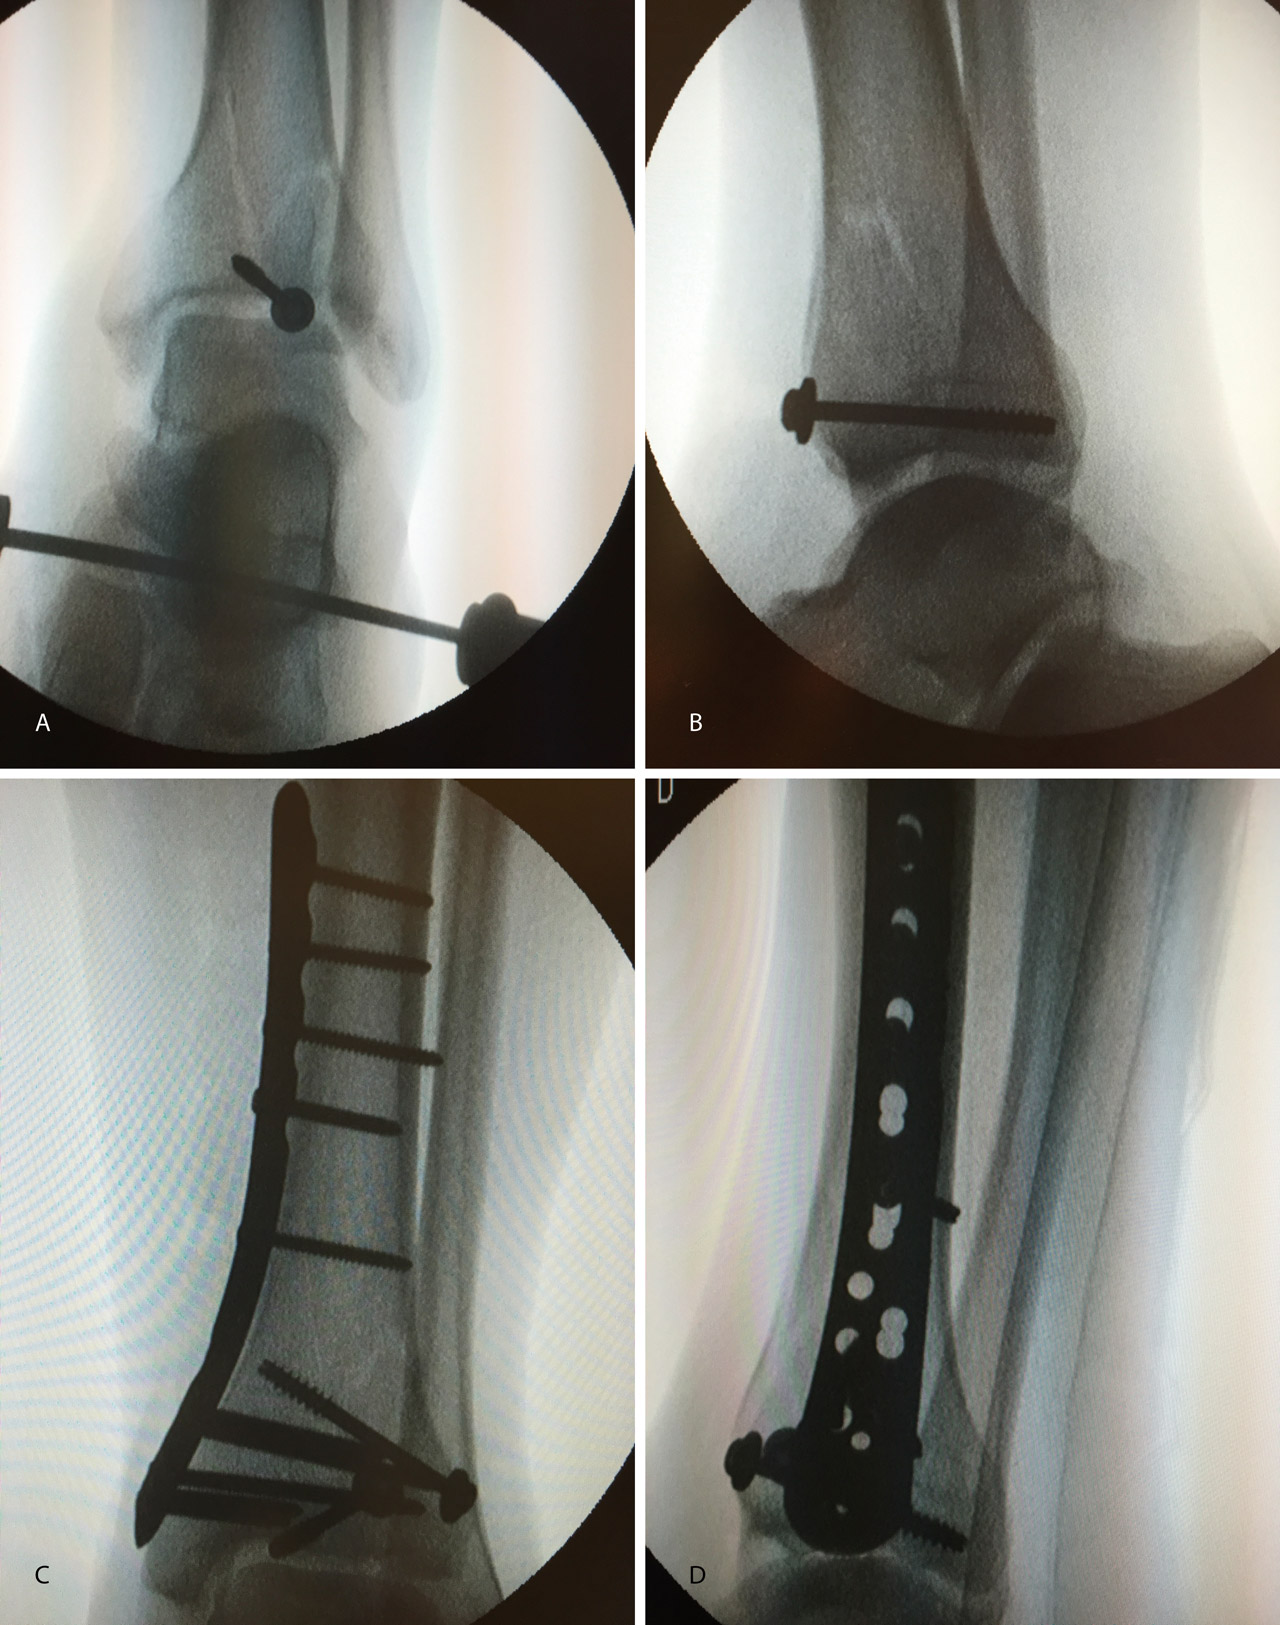

3. Fractura de tipo C: reducción artroscópica, fijación de la epífisis con tornillos canulados y fijación final de la epífisis a la diáfisis por técnica MIPO.

En este caso, es esencial observar las Rx con y sin tracción que nos indican cómo se va a comportar la fractura. Si la fractura es reductible en tracción, es muy probable que podamos realizar una osteosíntesis con restitución completa de la superficie articular. Al realizar la TC, apreciamos la disposición de los fragmentos para marcar una estrategia de reducción bajo control radioscópico y artroscópico, y colocación de los tornillos canulados que fijarán la epífisis distal de la tibia.

Posteriormente, colocaremos la placa en la tibia por vía MIPO realizando una incisión interna, separando la vena safena y deslizando la placa que se fija de manera provisional. Tras comprobar por radioscopia la buena posición del implante, se realiza la fijación definitiva con los tornillos que consideremos adecuados. En el caso de que tengamos que usar un fijador, este sustituye a la placa interna (Figuras 17 a 20).

Figura 17. Caso 3: fractura tipo C. Radiografías sin tracción y con tracción comprobando la reducción.

Figura 19. Colocación del tornillo en el Tillaux con la extremidad en tracción y posteriormente la placa MIPO (minimally invasive plate osteosynthesis).